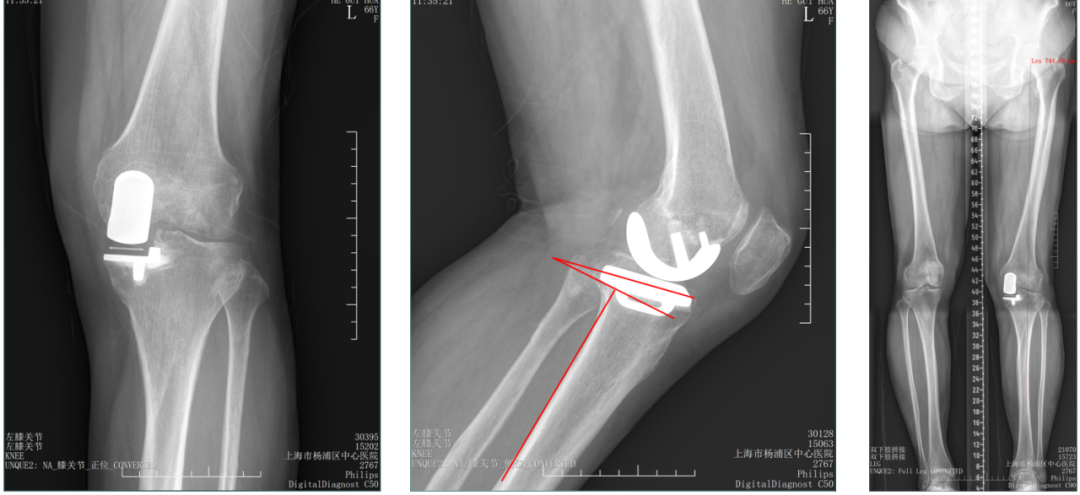

病例1:胫骨假体后倾角度>7°

问题:胫骨假体后倾角度12°,轻度膝外翻

病例1:胫骨假体翻修

UKA to UKA 更换胫骨假体